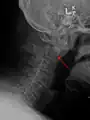

- Type 2 dens fracture